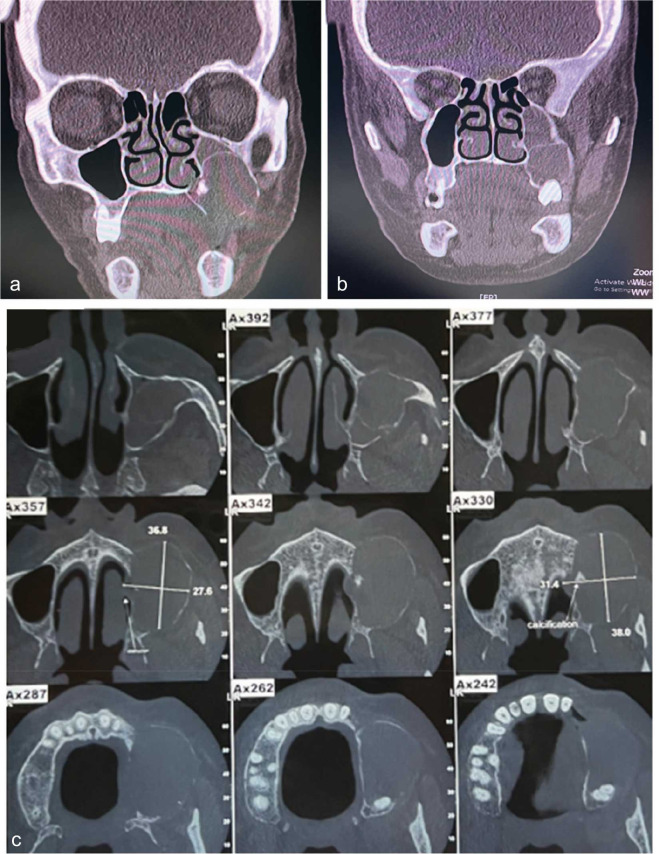

In the present study, we reported a 66-year-old woman with an uncommonly painful calcifying odontogenic cyst (COC) in the posterior region of the left side of the maxilla. The cyst was evaluated radiographically and histopathologically. The present case showed a multilocular cyst with a mixed internal structure. The most noticeable effects on the peripheral structures were elevated maxillary sinus floor, osteomeatal complex, and nasal obstruction. To better understand the impact of COC on the trabecular pattern of the surrounding bone, we performed fractal analysis on the panoramic images pre- and post-operatively. The expansion of COC can change the trabecular pattern, which subsequently can change the fractal dimension of the area. After histopathological confirmation of the diagnosis, the cyst was surgically removed.